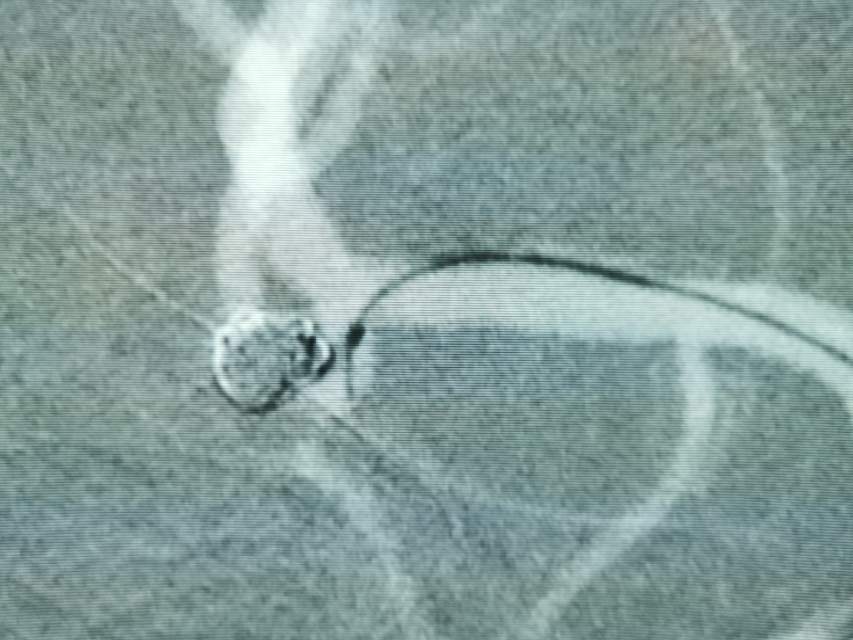

破裂的大脑中动脉动脉瘤二期支架植入

患者,中年男性,颅内动脉瘤破裂出血,急性期给予单纯弹簧圈大部致密栓塞(瘤颈少许残留),降低了急性期破裂出血的风险,急性期免除了使用抗血小板的顾虑和担心(如果使用支架),为了预防远期的复发,二期植入支架,就会安全多了